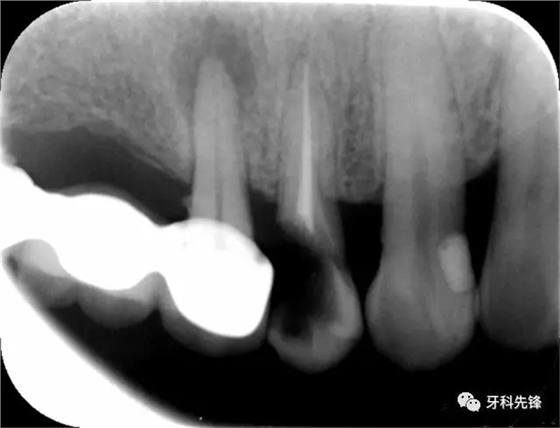

圖8治療術(shù)后X光片

640.webp (10).jpg

640.webp (11).jpg

640.webp (12).jpg